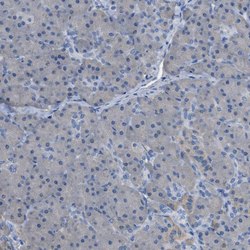

- Immunohistochemical staining of ASGR1 in human pancreas using ASGR1 Polyclonal Antibody (Product # PA5-52994) shows no positivity in exocrine glandular cells as expected.

- Immunohistochemical staining of ASGR1 in human colon using ASGR1 Polyclonal Antibody (Product # PA5-52994).